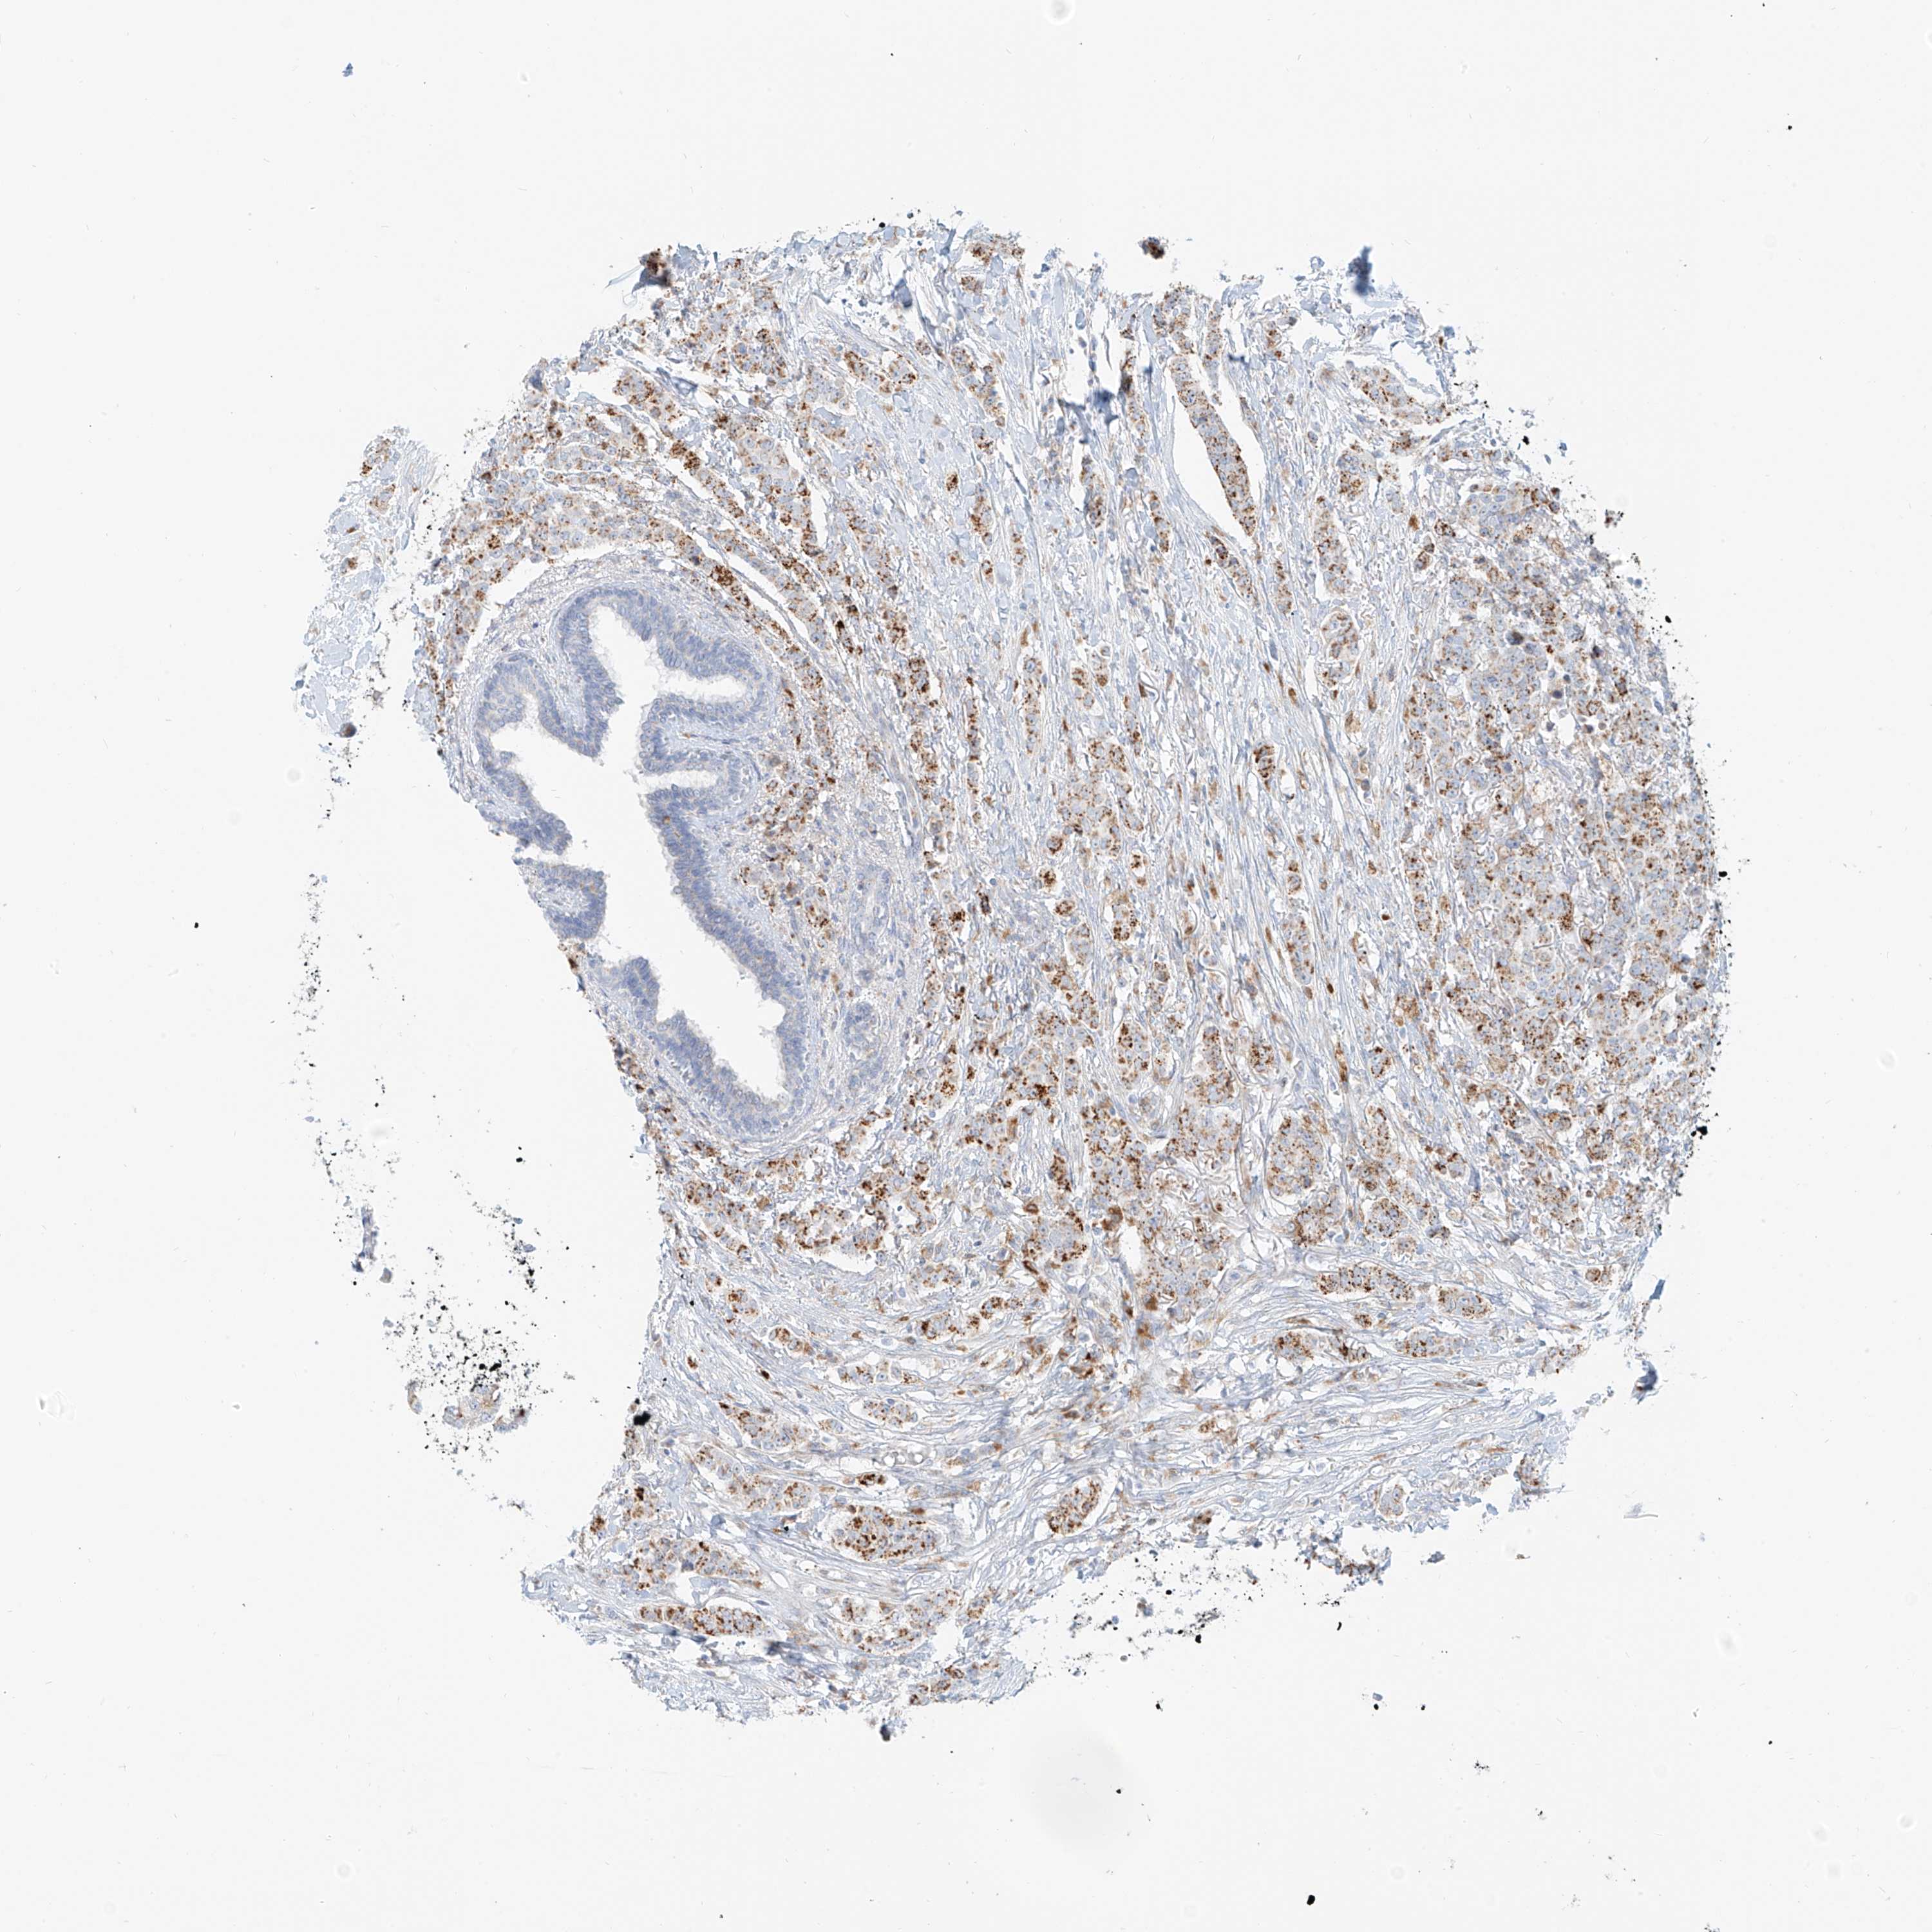

BRCA TCGA BRCA VALIDATION PROTEIN EXPRESSION